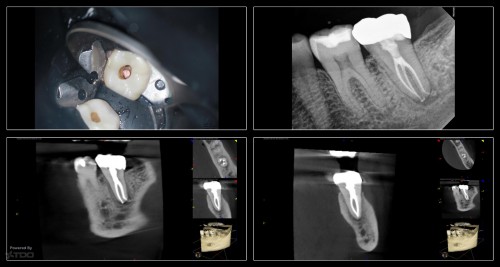

Collage-232332-Page00

This was a finish from last week.  The largest file used was a 20.  The innovation of the heat treated files allow us to be more conservative from the access to the instrumentation.